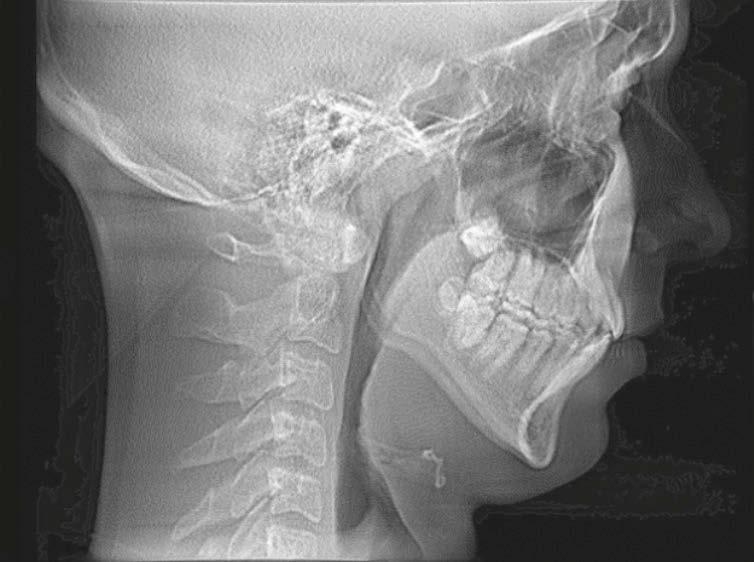

A pediatric-patient dedicated Sleep Medicine laboratory setting is difficult or impossible to find, setting aside what is considered the diagnostic gold standard, overnight PSG. Most screening questionnaires can be valuable as SRBD morbidity assessment tools and reliable for predicting increased risk. They are based solely upon identifying SRBD behavioral phenotypes known to be associated with suboptimal sleep hygiene (e.g., snoring, teeth grinding/bruxism, excessive bodily movements). The Sleep Clinical Record (SCR)15 is an exception because it relies on not only behavioral morbidity traits, but also some physical morbidity traits such as constrictive/retrusive and retrognathic jaw maldevelopments,16 which are known to be associated comorbidities with SRBD.17 Most of these physical traits can be classified as malocclusion phenotypes and generally are located within the interconnected craniofacial respiratory complex (CFRC)18 (Fig. 1) which was foreshadowed by Dr. LeRoy Johnson in the opening paragraph of

this review: ‘The face has evolved with the functions of mastication and respiration.’- L.J. 1921.

While the SCR goes further than most other screening assessment tools towards identification of some CFRC/SRBD co-morbidities, it is limited in its comprehensiveness. Ideally, in addition to screening for birth/perinatal history risk factors, such as pre-term birth,19,20 clinicians should have validated screening tools for identifying behavioral comorbidity traits, and for identification of physical risk phenotypes of the CFRC. The CHICAGO HEARTS screening tool combines these survey areas. (Fig. 2).

In a lecture held in 2018 at Boston University entitled ‘Sleep Disordered Breathing/Obstructive Sleep Apnea Symposium’,21 a new screening tool called C.H.I.C.A.G.O. H.E.A.R.T.S. (C.H.) had been introduced as potentially becoming the first validated screening device specifically designed to identify CFRC physical traits that can often be comorbid with SRBD. Several of these traits are listed within the C.H. acronym (Fig. 2). For instance, under the first letter ‘C’ are listed: Crossbite 22,23 Fig. 3 and Crowded Pharynx;24,25 ‘H’: Hyper-divergent growth (Fig. 4),16 Hypertrophic tonsils and/or adenoids;26,27 ‘I’: Incompetent lips;28 ‘C’: Constricted arches (Fig. 5);23,29,30 ‘A’: Airway anatomy (Fig. 6);22,31 ‘G’: Grinding teeth (bruxism)32 and Gonial angle excess;33 ‘O’: Overweight child34 and Obtuse nose-lip angle( NLA);35 ‘H’: Highly-vaulted palate;36 ‘E’: Ezcema-atopia37 and Eye appearance-venous pooling38 and scleral show;39 ‘A’: Anterior open-bite

(Fig. 8):40 ‘R’: Retrognathia (Fig. 9) (mandible16 and/or maxilla);41 ‘T’: Tongue posture,42 tie (tether),43,44 scalloping;45 ‘S’: Septal deviation46 and night Sweats (diaphoresis).47